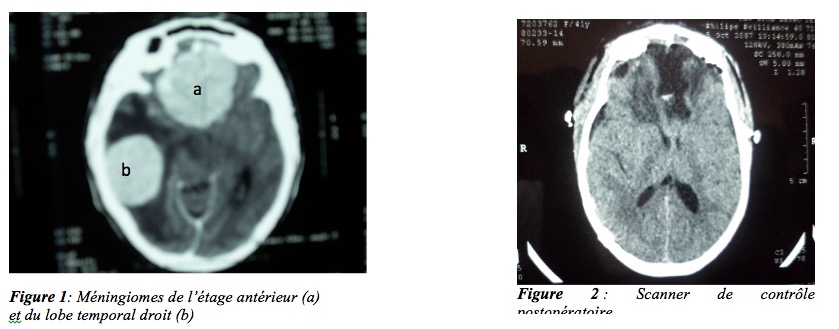

Au huitième jour après la sortie, la reprise des céphalées handicapantes a motivé une nouvelle consultation de l’anesthésiste. L’interrogatoire retrouve une notion de flou visuel et des troubles de l’humeur associée à une alternance d’indifférence et de nervosité. Les céphalées étaient toujours considérées comme liées à la rachianesthésie malgré les troubles neurologiques associés. Un blood-patch n’a pas été réalisé. La patiente a été traitée en ambulatoire par voie orale avec une association paracétamol-caféine et hydroxyzine. Après cette prescription, la patiente a été perdue de vue et revue seulement trois mois après avec des céphalées toujours persistantes. Les troubles visuels et de l’humeur s’étaient accentués. Une consultation en ophtalmologie puis en neurochirurgie ont été alors réalisées. L’examen du fond d’œil révèle un œdème papillaire au stade IV. Sur le plan neurologique, on retrouvait une discrète instabilité de la marche et un syndrome frontal associant une hyper émotivité, un état de prostration avec épisode de mélancolie et une notion d’incontinence urinaire. La patiente présentait aussi des troubles de l’humeur et des pleurs inopinés. L’étude plus approfondie des antécédents à ce stade a retrouvé une notion de céphalées chroniques intermittentes remontant à plus de 3 ans ainsi qu’une crise convulsive passagère au cours d’une grossesse antérieure. Le scanner cérébral réalisé a objectivé deux lésions tumorales majeures. La première siège à l’étage antérieur. Elle est globalement sphérique, 5 centimètres de diamètre. La deuxième lésion est pétreuse et sus pétreuse droite, d’allure similaire mais cernée d’une importante réaction œdémateuse. Elle est responsable d’un effet de masse important sur le système ventriculaire, à l’origine d’un engagement sous falcoriel gauche supérieur à 12 millimètres. Les deux lésions sont iso-denses et intensément rehaussées par le produit de contraste. On note enfin, une discrète hydrocéphalie obstructive (Figures 1 et 2).

Ces lésions sont évocatrices de méningiomes cérébraux. Une indication opératoire a été retenue. L’intervention réalisée en deux temps, à quinze jours d’intervalle, a consisté en l’abord successif de la lésion pétreuse puis de la lésion de l’étage antérieur. Les examens anatomopathologiques postopératoires ont confirmé le diagnostic de méningiomes. Les suites opératoires ont été excellentes avec disparition complète des céphalées, des troubles visuels et neurologiques, autorisant une complète autonomie et la reprise des activités professionnelles au bout de six mois. Le bilan neuro- radiologique de contrôle a confirmé l’exérèse complète des deux lésions. (Figure 3).